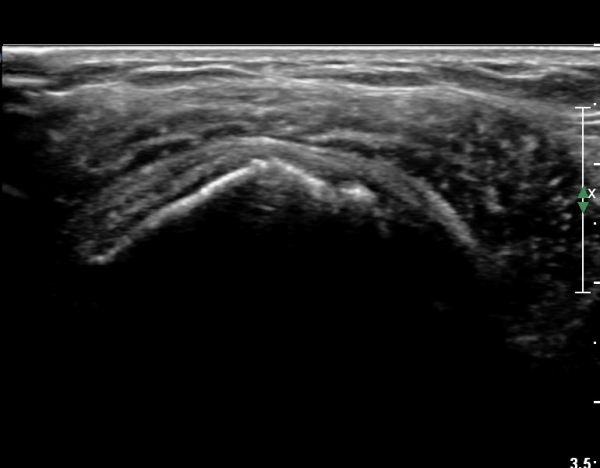

ȸÀü±Ù°³°£°Ý(rotator cuff interval) Ⱦ´Ü¸é°Ë»ç¿¡¼­ ÀÌµÎ¹Ú±Ù°Ç ¿ÜÃø¿¡ ±Ø»ó°ÇÀÌ °üÂûµÇÁö ¾Ê°í

´ë°áÀý Ç¥ÃþÀÇ »À°¡ ¿ïÅüºÒÅüÇÏ°Ô º¯ÇÏ¿´´Ù(±×¸² 1, 2)

ÀÌ´Â ½ÉÇÑ Ãæµ¹ÁõÈıºÀÇ °á°úÀ̰í ȸÀü±Ù°³ ÆÄ¿­À» °­·ÂÈ÷ ¾Ï½ÃÇÏ´Â ¼Ò°ßÀÌ´Ù.